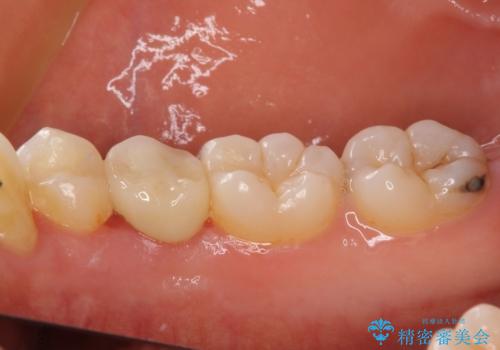

- 神経を抜く処置の後に装着したプラスチックのクラウンが外れてしまったとのことで来院された患者様です。

患者様自身、神経の取り除かれた歯はしっかりと製作されたクラウンを装着するべきと理解していただいていたため、オールセラミッククラウンにて補綴治療することとしました。

丈夫なクラウンを装着できただけでなく、形態や色調も自然に仕上げることができました。